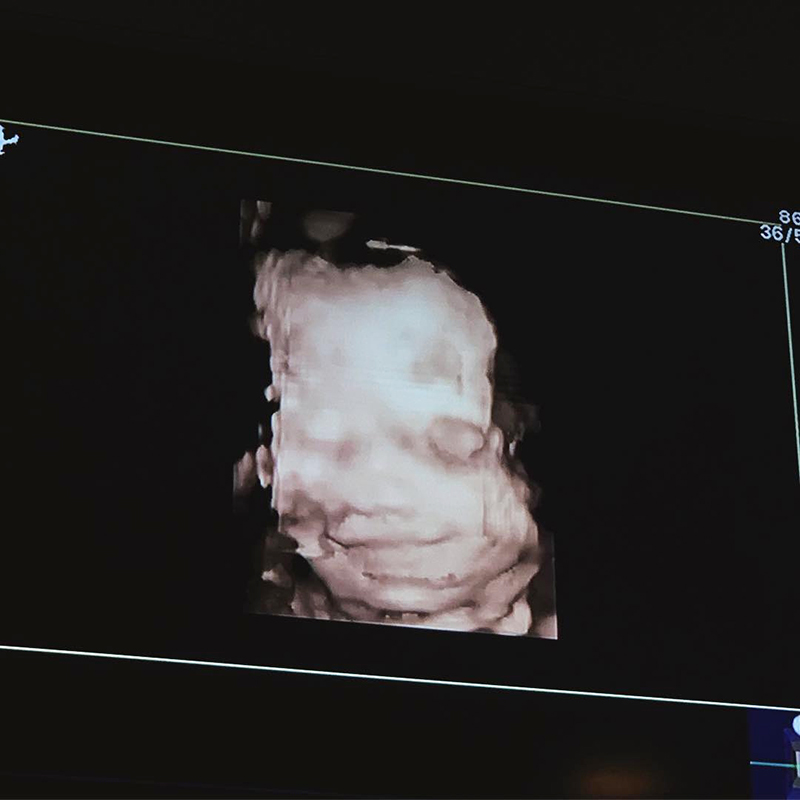

อุ้ม ลักขณา ปลื้มมาก อัลตราซาวด์น้องดิสนีย์ พบลูกสาวยิ้มสวยมาตั้งแต่อยู่ในท้อง ออกมาต้องเป็นคนน่ารักอารมณ์ดีแน่ ๆ

ล่าสุด 24 มกราคม 2562 สาวอุ้มก็ได้เผยภาพอัลตราซาวด์ลูกสาว ที่อยู่ในครรภ์มาแล้ว 27 สัปดาห์ ซึ่งสิ่งที่เห็นได้ชัดเลยก็คือ น้องดิสนีย์ยิ้มแฉ่งแบบสวย ๆ หวาน ๆ ตั้งแต่อยู่ในท้อง แถมมีแต่คนเข้ามาบอกว่าน้องหน้าเหมือนคุณแม่เลย โดยเฉพาะรอยยิ้มที่ได้คุณแม่มาอย่างไรอย่างนั้น

ยิ้มตั้งแต่ในท้องแบบนี้ เกิดมาคงเป็นหนูน้อยอารมณ์ดีนะคะเนี่ย